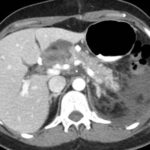

Tomografía de abdomen y pelvis con cte ev: del 13/10/2023.

Complicaciones posquirúrgicas

Tomografía de abdomen con cte ev: del 20/10/2023.

Tomografía de abdomen con cte ev: del 26/10/2023.